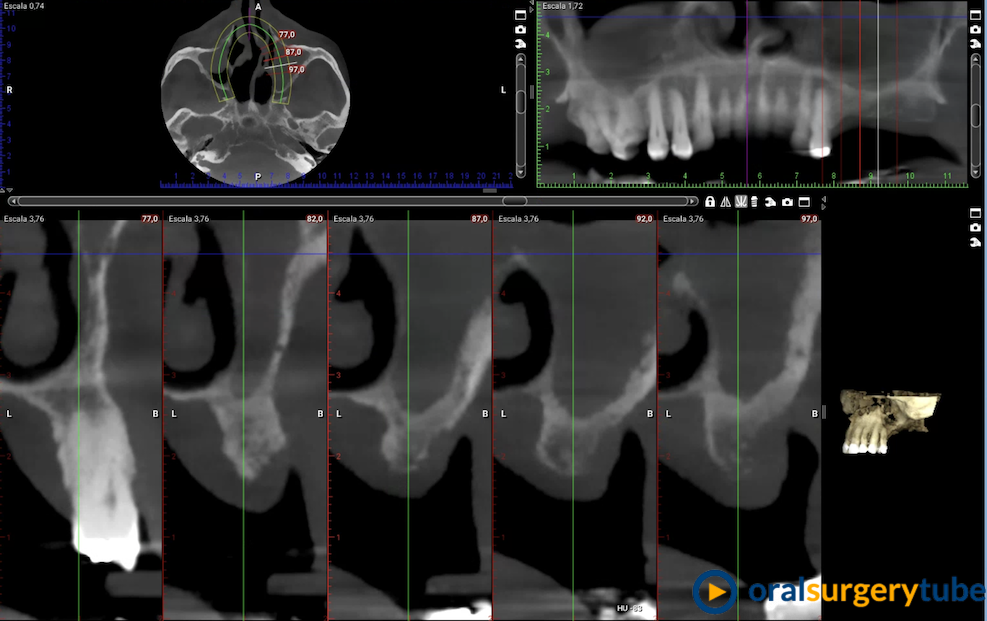

Comunicación Bucosinusal tras elevación de seno